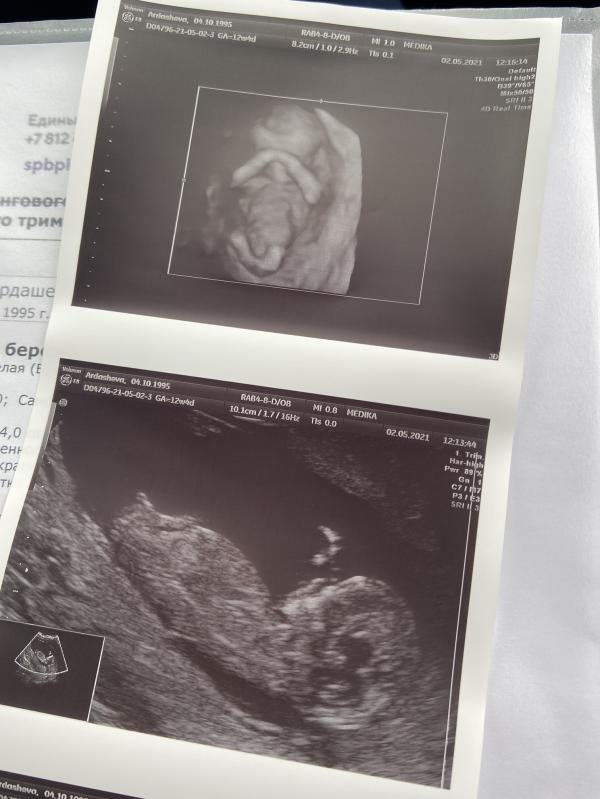

🌺02.05.2021 🌺

Сделали первое скрининговое узи, в 12н4д. По результатам все показатели в норме, предположительно ждём девочку🌸